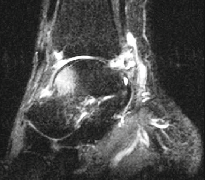

---MRI检查

MRI检查:可以清楚显示踝关节周围软组织、韧带、软骨、骨结构的改变,对踝关节损伤严重程度和滑膜病变做出良好判断,为踝关节撞击征的诊断提供重要参考依据。

(MRI检查可见关节前方距骨水肿,后方出现软组织撞击、局部积液肿胀)